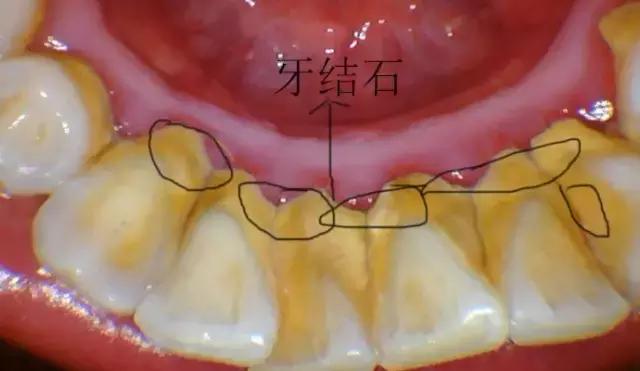

原因很简单,原来牙齿有藏污纳垢的牙石包裹,牙龈经常发炎、出血,牙骨质也可能被破坏了;洗掉牙石后,牙齿恢复原貌,但由于牙龈退缩,导致牙根位置的牙本质暴露出来,一碰到冷热酸甜,就会让人酸软不适。

对于牙结石较多较厚、药物抗炎效果欠佳或脱敏治疗欠佳的患者,做一次对这些患者来说,太辛苦,而分几次洁牙,“化整为零”,患者容易接受,而且在洁牙间期,还可继续进行抗炎治疗或脱敏治疗,这可大大减轻酸痛感。

4、定期洁牙

洗牙后之所以让人容易有牙缝变大的感觉,是因为在洗牙的过程中,把堆积在牙龈表面、牙缝间的牙结石通过超声波震动方式震碎、清除,而使得舌头在碰触牙齿时,不再受到牙结石干扰,可直接碰触牙缝所致。其实,这些牙缝是本身早已存在的,与洗牙并无关。